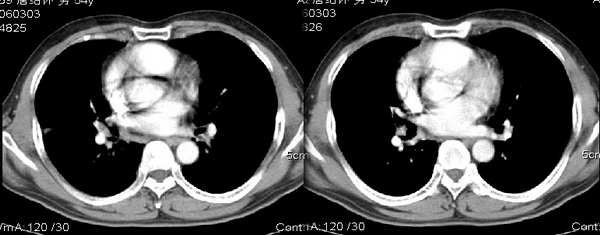

男54岁咳嗽咯痰2w,外院胸片示“右上大叶性肺炎抗炎治疗后部分吸收

右肺上叶少量间质炎性表现,结合病史为大叶性肺炎未吸收完表现。

结合病史,右上肺病变考虑炎症,继续抗炎治疗后复查;

该病人54岁,胸膜下可见多个类圆形透亮影,是不是还要考虑慢性/弥漫性肺疾病可能?

请问右中叶支气管开口旁不强化结节影是什么?

右上叶支气管变窄.ca?